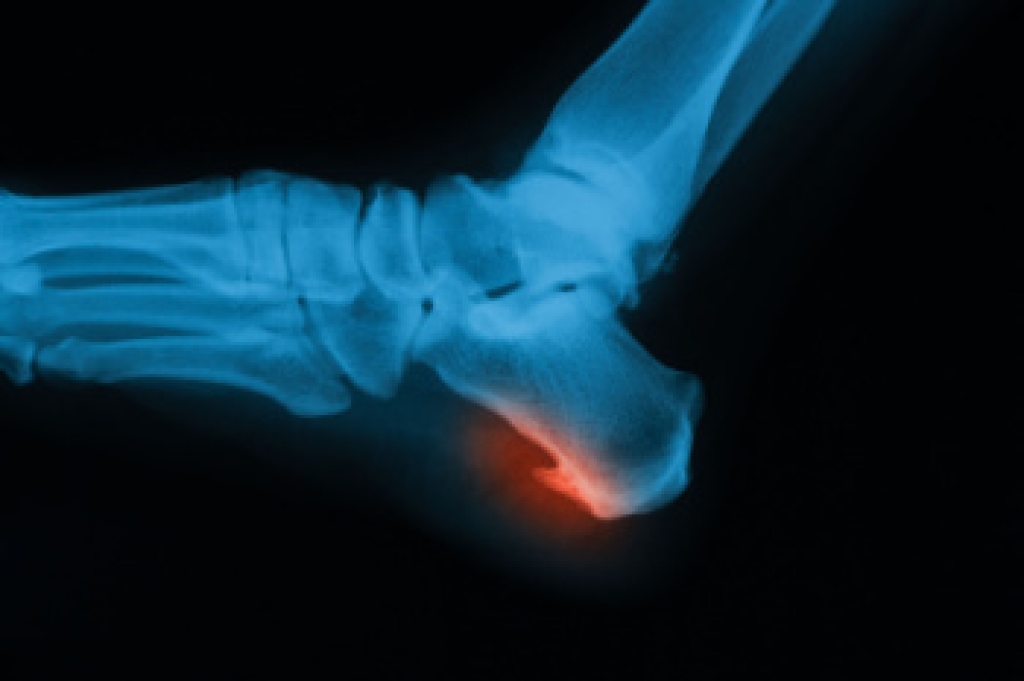

In many cases the cause of toe pain is obvious, but in others, a podiatrist may want to use more advanced methods to determine the problem. These can range from simple visual inspections and sensation tests to X-rays and MRI scans. Prior medical history, family medical history, and any recent physical traumatic events will all be taken into consideration for a proper diagnosis.